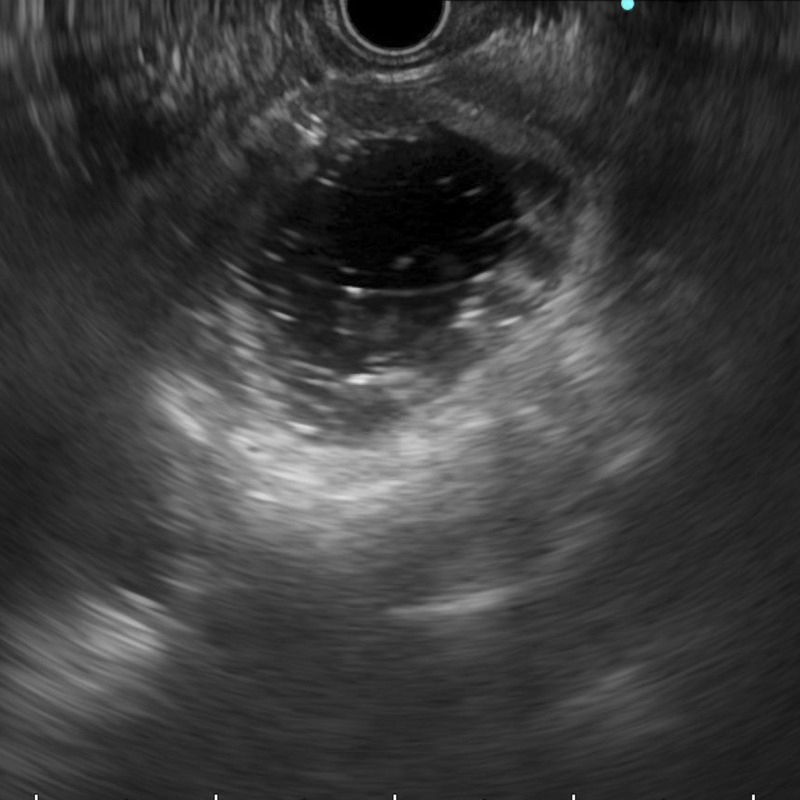

十二指肠支架置入术后恶性十二指肠梗阻复发:eus引导胃空肠吻合术成功治疗(附视频)。

Recurrence of malignant duodenal obstruction following duodenal stenting: successful management through EUS-guided gastrojejunostomy (with videos).